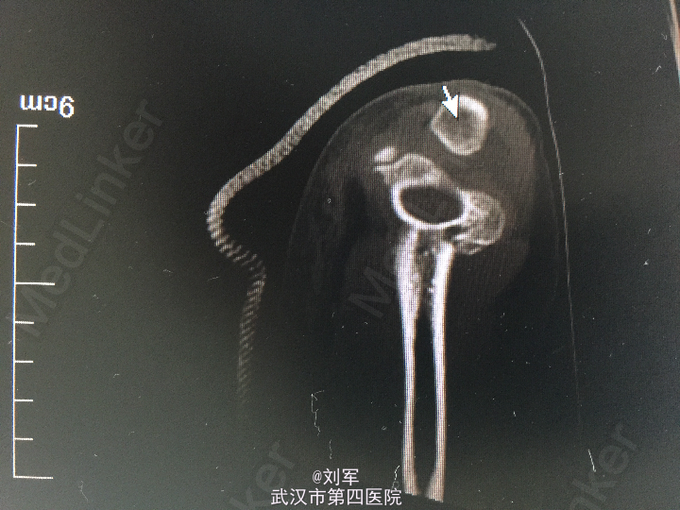

患儿,女,7岁九个月。因“外伤后右肘肿痛、畸形3小时”入院。三小时前,患儿玩耍时不慎摔倒,致伤右肘关节,当即肿痛,畸形,伴活动受限。被家长送入我院,门诊拍片后,遂以:右肱骨髁上骨折收住我科。起病来,神志清,未进食,二便未解。

PE:右肘关节肿胀,畸形,压痛。右环、小指感觉减退,指端红润。 辅助检查:X-ray及CT片:右肱骨髁上骨折,成角畸形。

诊断:右肱骨髁上骨折、尺神经损伤 入院第二天行开放复位内固定术+尺神经探查术。